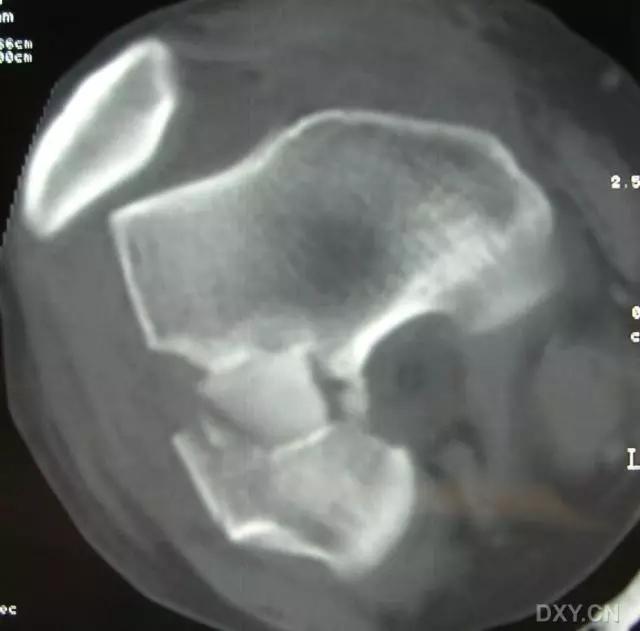

12. Cedell 骨折

距骨后内侧结节骨折。

Cedell 骨折的 CT 片 (来源:Fracture of the posterior medial tubercle of the talus :A case report and review of the literature. Acta Orthop. Belg., 2007, 73, 804-806)